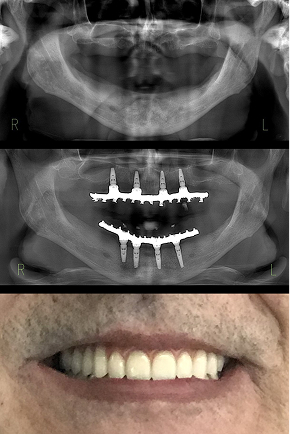

Protocolo em maxila e mandíbula atrófica sem enxerto.